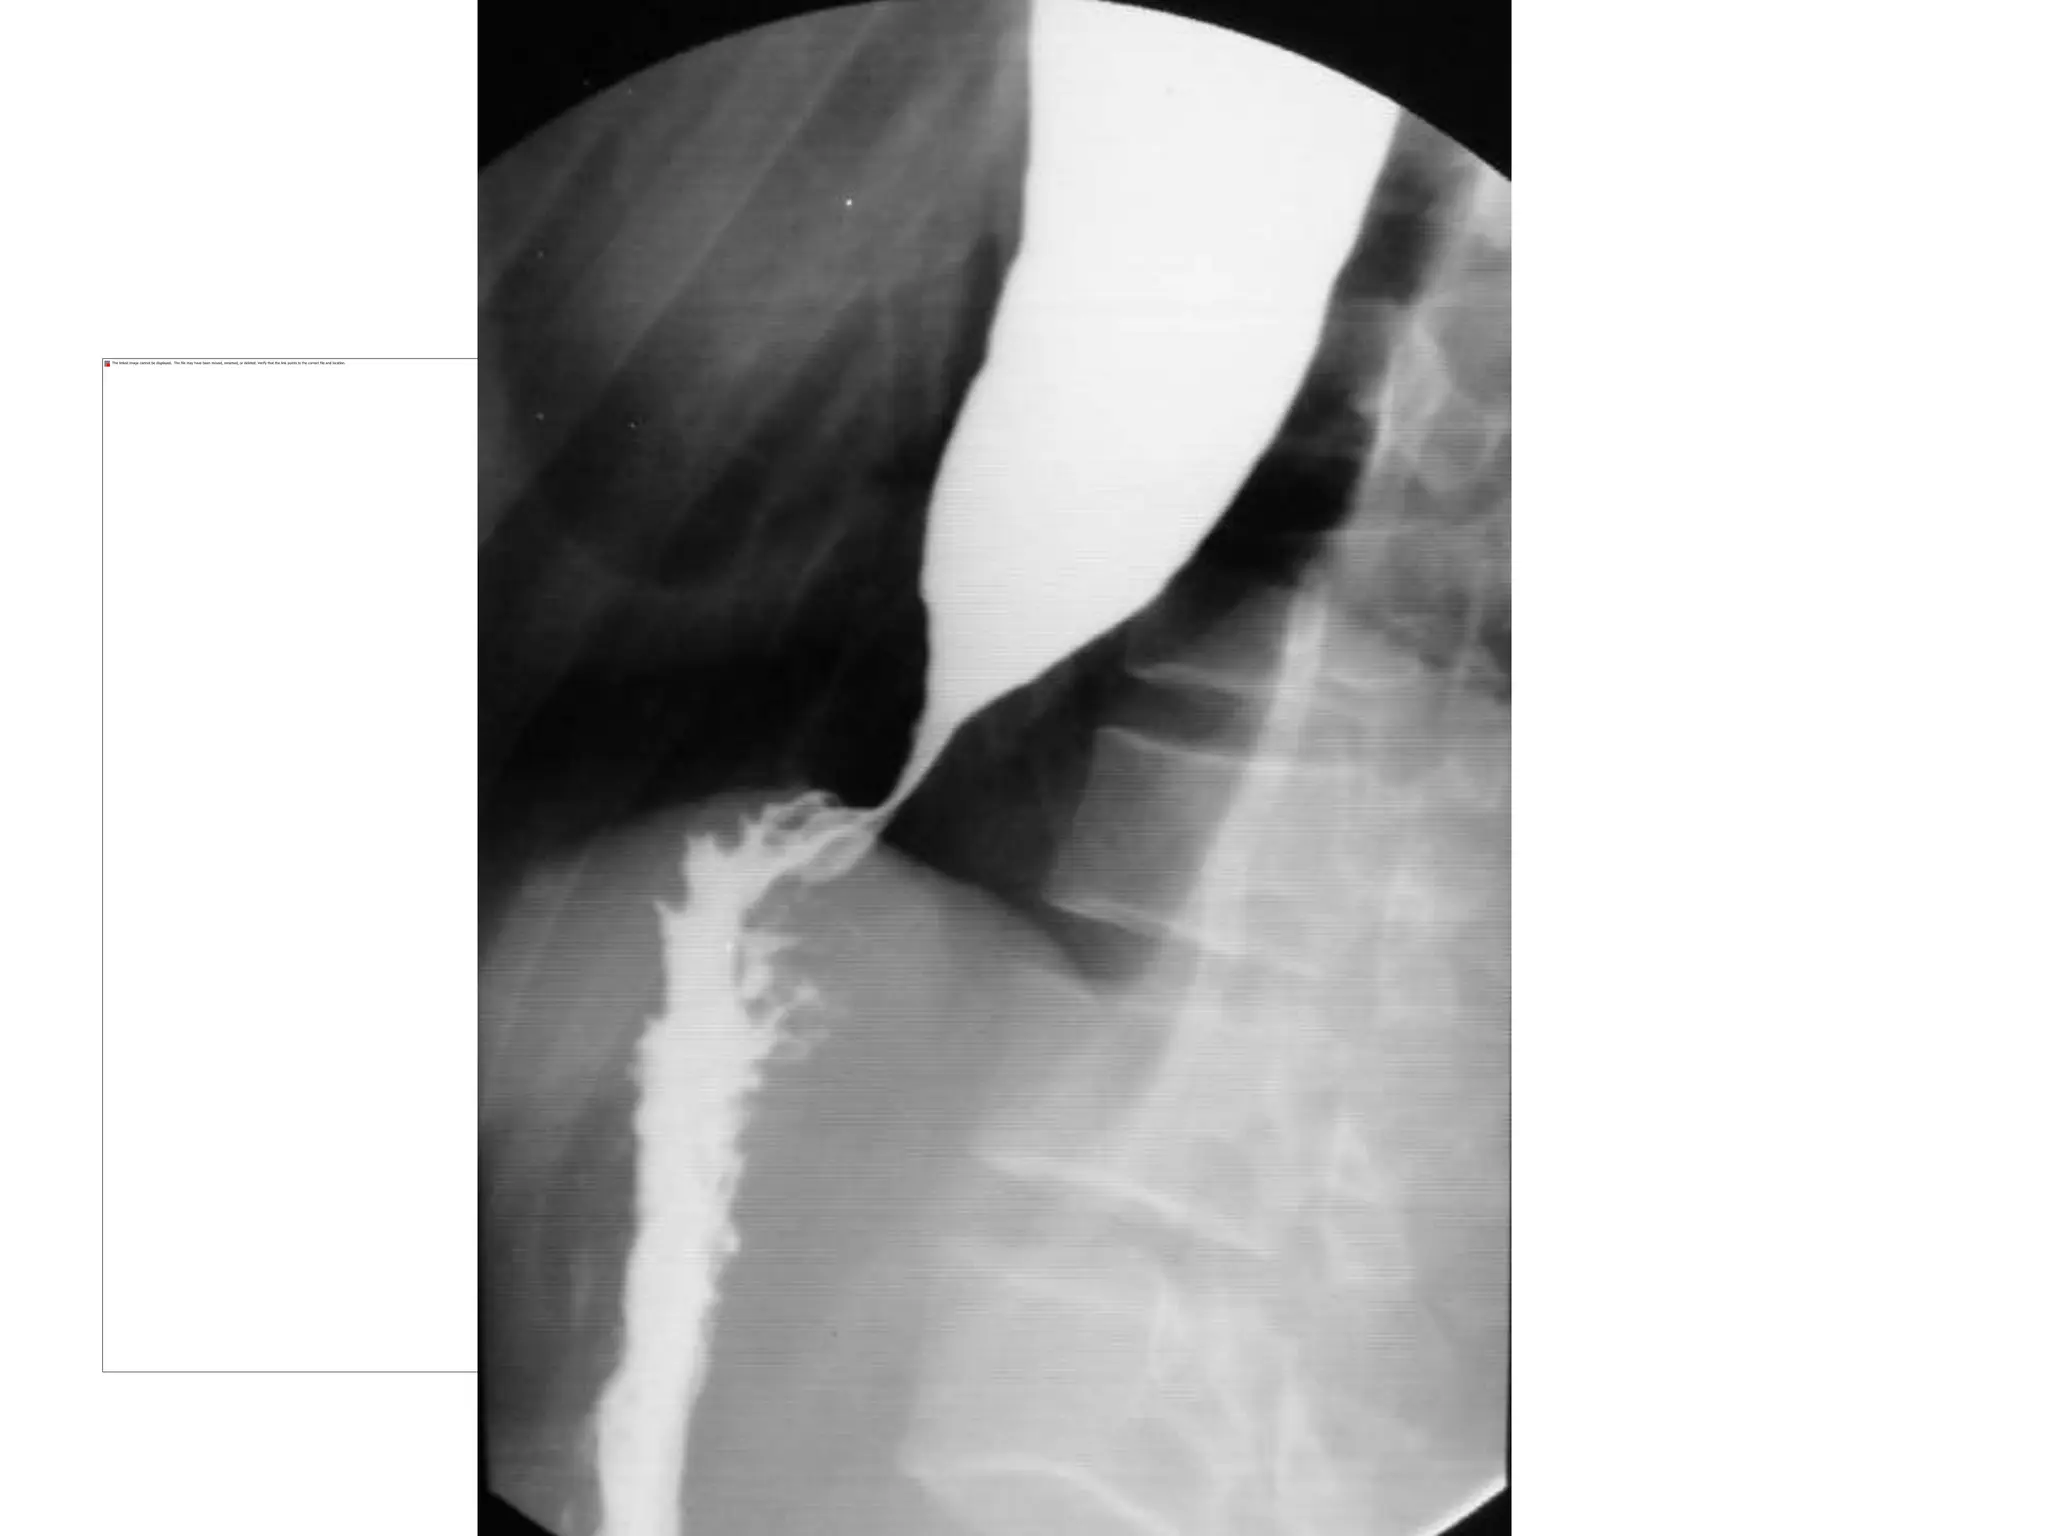

Esophageal stage of swallowing

• Passage of food from

Pharynx to Stomach

Achalasia

• Loss of inhibitory neurons in myenteric plexus

• Esophageal stasis leads to infection of

esophagus

Treatment

• Dilation

• Antispasmodic drug